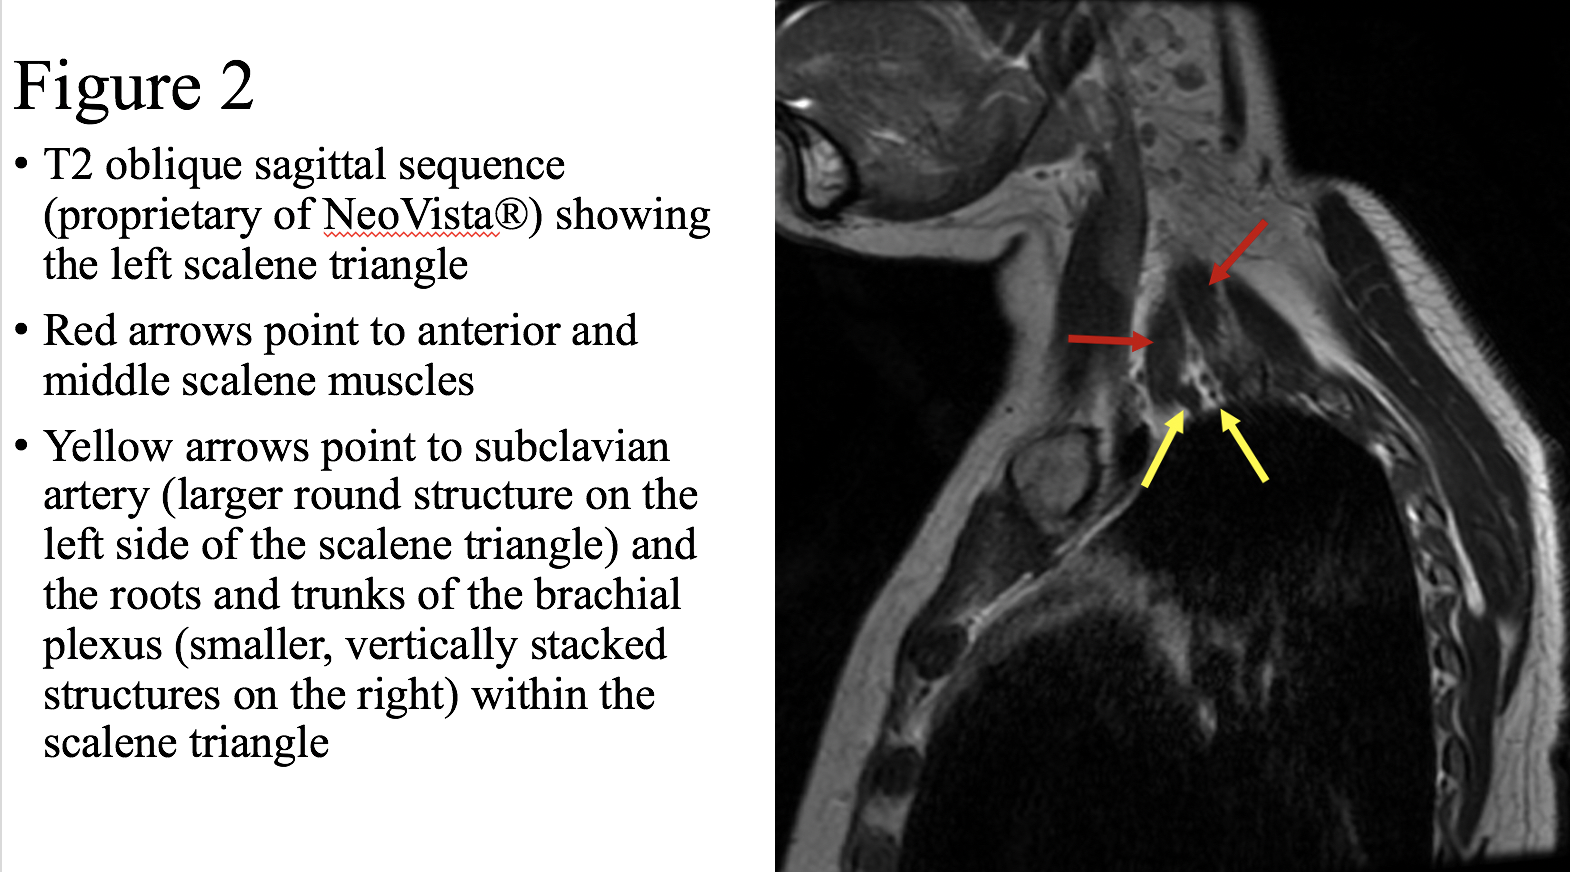

We present a patient with headaches, bilateral arm pain, and bilateral weakness. She has a positive EAST test bilaterally at 30 seconds. Right arm pain is worse with arms up, and this pain is reproduced by compression of the right costo-clavicular ligament. Left arm pain is worse with arms up, with weaker grip on Grip-X testing in the arm-up position, with reproduction of left radiating arm pain on compression of the left scalene muscles. Imaging demonstrates a narrowed costoclavicular interval on the right (1.0 cm, less narrowed on the left) with the arms abducted but no compression when the arms are down (Figure 1, Figure 2). This patient has two different types of TOS, both NTOS and ATOS, and because her story doesn’t fall classically into what we call “Occam’s Razor”, she was given the diagnosis of fibromyalgia by her neurologist.

Figure 2: NeoVista imaging showing T2 oblique sagittal sequence.